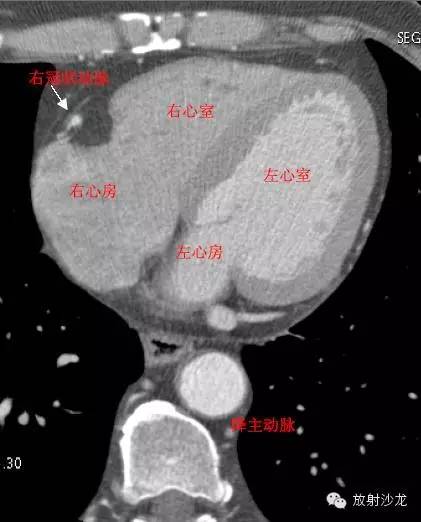

LA -Left Atrium左心房

RA -Right Atrium右心房

LV -Left Ventricle左心室

RV -Right Ventricle右心室

D. Aorta-Descending Aorta降主动脉

RCA -Right Coronary Artery 右冠状动脉